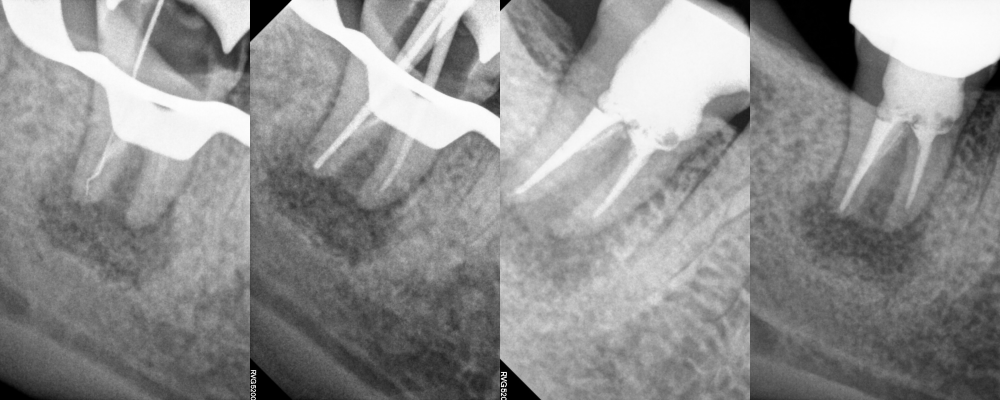

진료 과정

먼저 자연치를 손상시키지 않도록

조심스럽게 발치했습니다.

발치된 상태로 구강 외에서

정밀하게 검사하면서

염증 조직을 제거하는데요.

관찰 결과, 자연치의 형태가 C형으로

특수한 구조를 가지고 있습니다.

이 오목한 부위에 염증조직이

단단하게 달라붙어 있는 것을

확인할 수 있습니다.

이 부분이 바로 신경치료로도

제거되지 않았던 감염 부위인데요.

치근단 부위를 2~3mm 절단한 후

감염된 조직과 오염된 상아질을 제거합니다.

특히 C형 구조의 오목한 부분에

숨어있던 염증조직을

제거하는 것이 치료의 핵심인데요.

이후 MTA를 이용하여

치근단 부위를 밀봉했습니다.